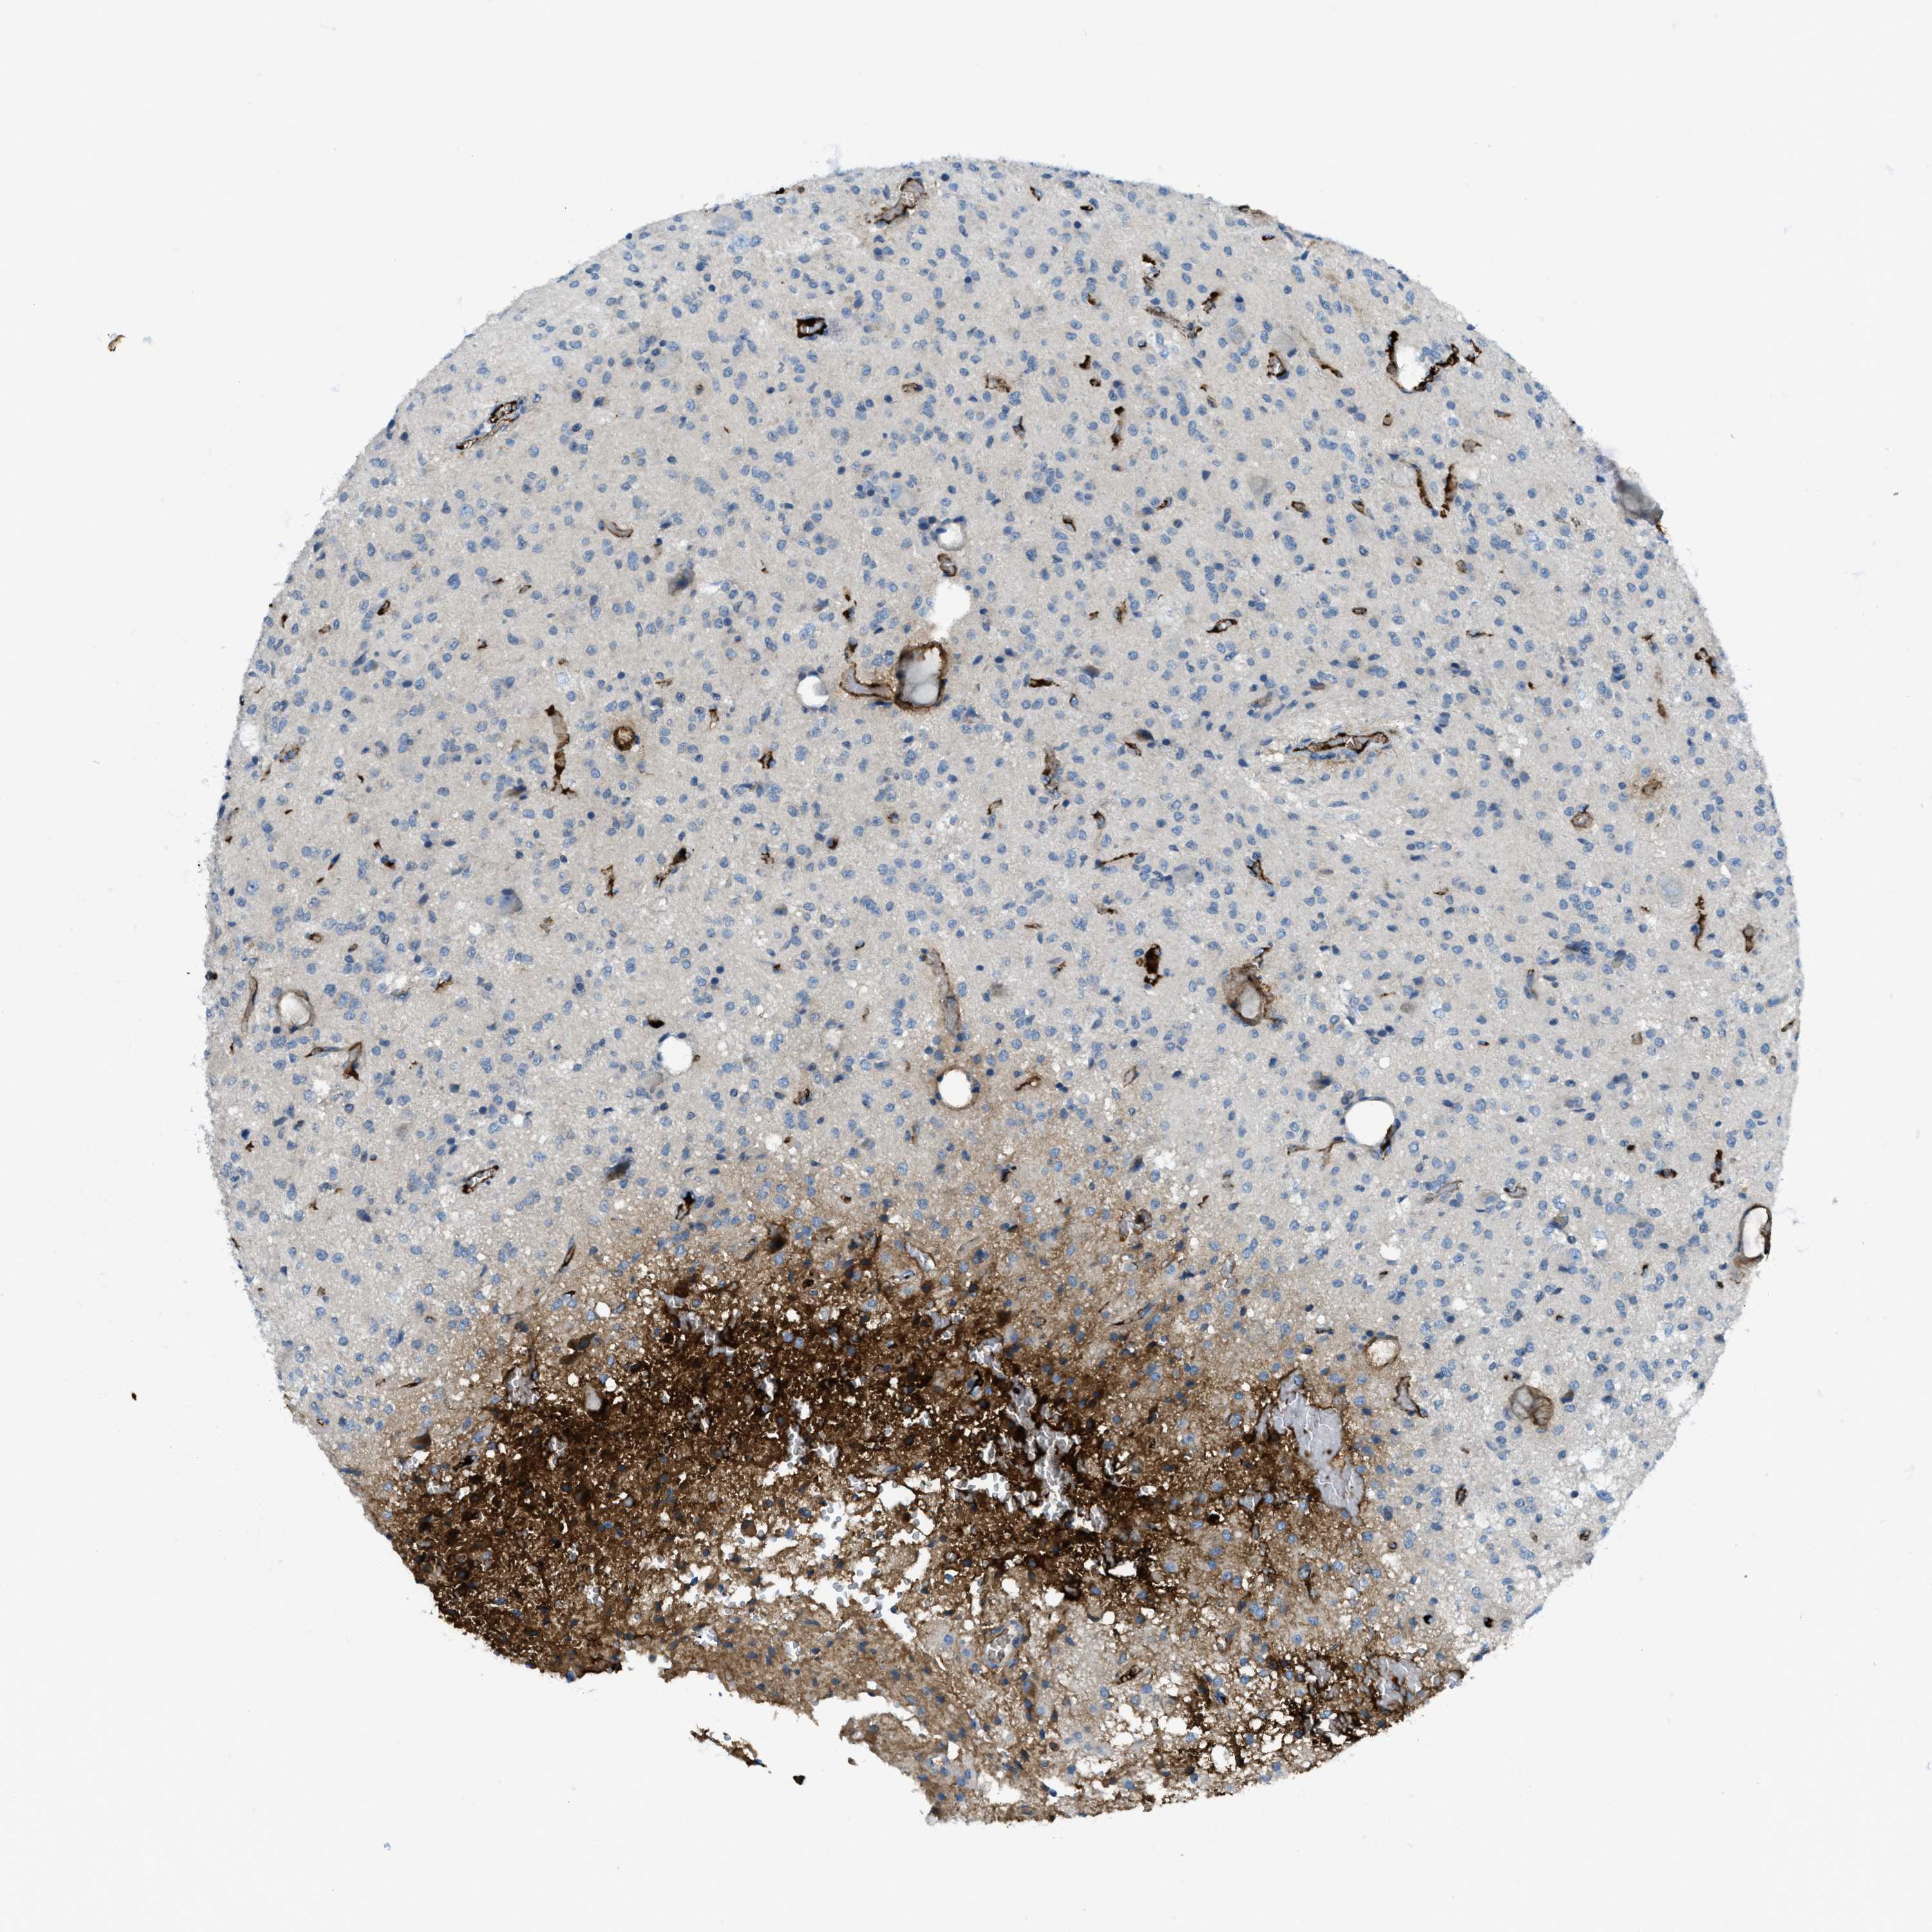

GLIOMA - Protein expressioni

A mouse-over function shows sample information and annotation data. Click on an image to view it in a full screen mode. Samples can be filtered based on level of antibody staining by selecting one or several of the following categories: high, medium, low and not detected. The assay and annotation is described here.

Note that samples used for immunohistochemistry by the Human Protein Atlas do not correspond to samples in the TCGA dataset.

Antibody stainingi

Antibody staining in the annotated cell types in the current human tissue is reported as not detected, low, medium, or high, based on conventional immunohistochemistry profiling in selected tissues. This score is based on the combination of the staining intensity and fraction of stained cells.

Each image is clickable and will lead to virtual microscopy that enables deeper exploration of all samples and also displays staining intensity scores, fraction scores and subcellular localization as well as patient and tissue information for each sample.

Antibody HPA017750

Staining

High

Medium

Low

Not detected

Intensity

Strong

Moderate

Weak

Negative

Quantity

>75%

75%-25%

<25%

None

Location

Nuclear

Cytoplasmic/membranous

Cytoplasmic/membranous,nuclear

Glioma, malignant, High grade

Glioma, malignant, Low grade